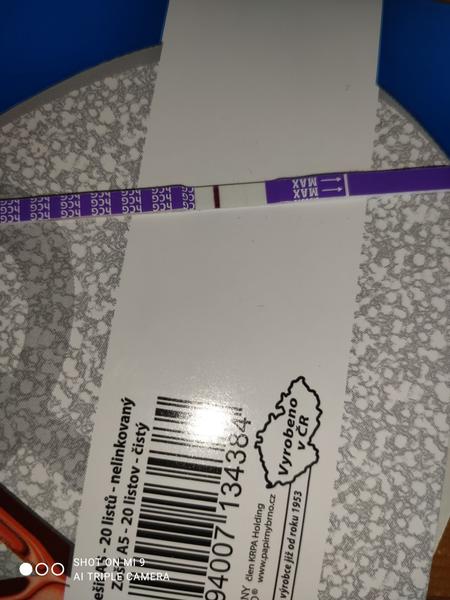

Je to duch či ryska?

Ahoj je to duch či ryska? Skúšala som to dať i do negatívu. Mám 10 dní od styku.

Za mna negat.

Tak ja patrím k tým čo má asi dobré oči 🤣 na každej fotke vidím samozrejme slabulinko ale niečo tam je ak to je do ružová tak sa ale neteš moc ešte stále nemáš nič vyhráte .o 2 dní testuje verím že tie čo nevidia už uvidia

Treba skúsiť iný test pozajtra ráno. Toto je Mamatest a keby tam aj bola naznačená čiarka, pravdepodobne iba falošne pozitívna.

Nie je tam ani duch ani kanalik